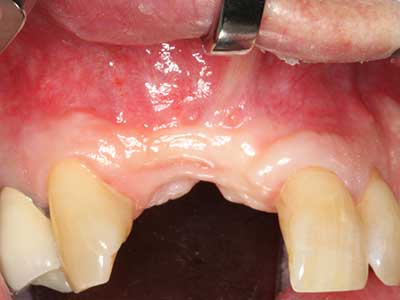

Fig. 2: Vertical and horizontal lateral maxillary defect with a high smile line with indication for pre-implant reconstruction.

Fig. 12: After six months of healing, the alveolar ridge is vital and sufficiently dimensioned in all planes.